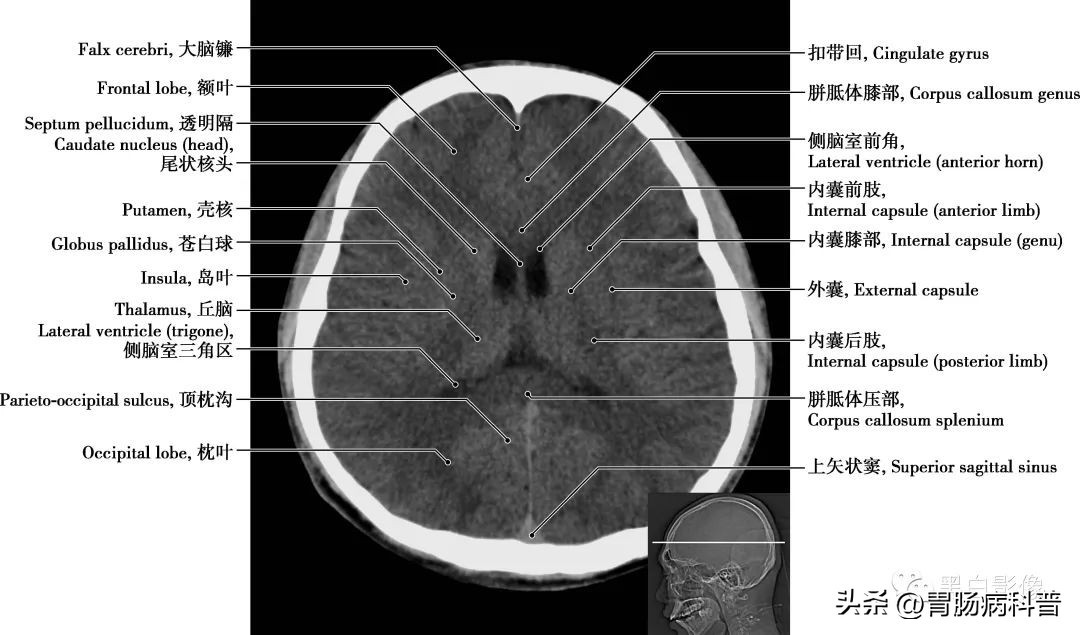

图1-1-8 经胼胝体膝部轴位切面

尾状核 位于丘脑背外侧,呈“C”形,全长伴随侧脑室,分头、体、尾三部分,尾状核和壳称新纹状体。尾状核与随意运动的稳定、肌紧张的调节密切相关,并有认知功能;受损可导致多种运动和认知障碍,新纹状体病变可导致舞蹈症